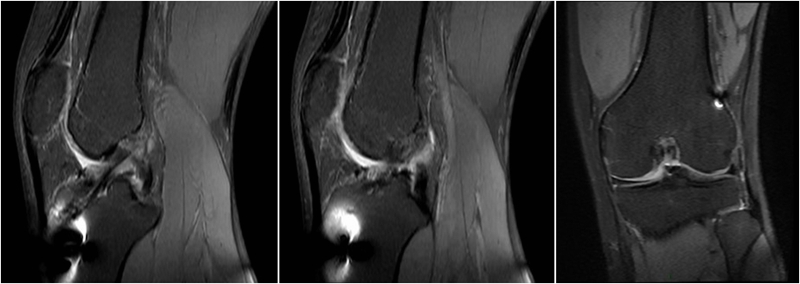

MRI检查评估ACL-R术后——韧带连续性信号好、方向好、愈合快,没有Cyclops综合征。

术后MRI